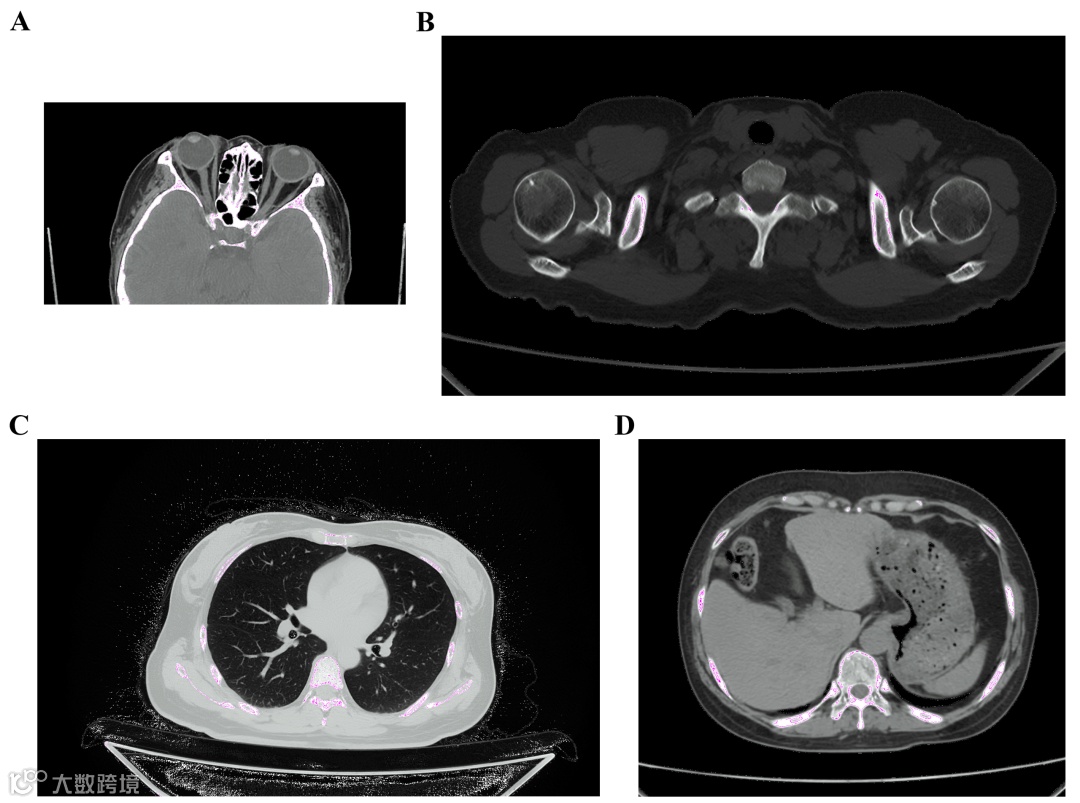

在志愿者临床扫描中,这款静态 CT 对眼部、骨关节、胸部、腹部等部位的成像表现惊艳,能清晰显示传统 CT 难以捕捉的精细结构:

眼部:清晰呈现眶环、晶状体、内外直肌及筛窦等细微结构,颞肌筋膜非常连续,与肌肉分层很好,皮肤,皮下组织,脂肪,肌肉分界清晰;

胸部:精准显示肺叶间裂、肺纹理、胸膜下及胸膜外特征,可捕捉 5mm 以下肺结节的空洞征象;

腹部:肝、脾、胃等脏器边界清晰,周围脂肪结构辨识度高。

图 3 临床扫描成像图